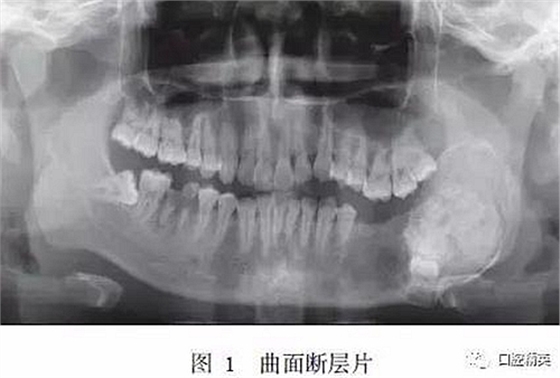

入院時??撇轶w:患者面型不對稱,開口度正常,開口型偏左側(cè)。左下頜膨隆明顯,范圍約5.0 cm×3.0 cm,向前延伸至D5根尖處,向后延伸至下頜升支,質(zhì)硬,觸之無乒乓樣感??趦?nèi)檢查示D5~D8缺失,左側(cè)頜下有一腫大淋巴結(jié),質(zhì)硬,活動,大小約1.5 cm×1.5 cm。曲面斷層片示:左下頜D4根尖區(qū)至左下頜升支乙狀切跡下方可見一異常高密度團塊影,團塊中心密度不均勻,病變邊緣光滑,周緣可見低密度條帶影包繞,D5~D8牙埋伏阻生于病變內(nèi),似不規(guī)則小牙體征象,病變區(qū)頜骨向頰舌向膨隆明顯,下頜神經(jīng)管受壓后向下移位(圖1)。